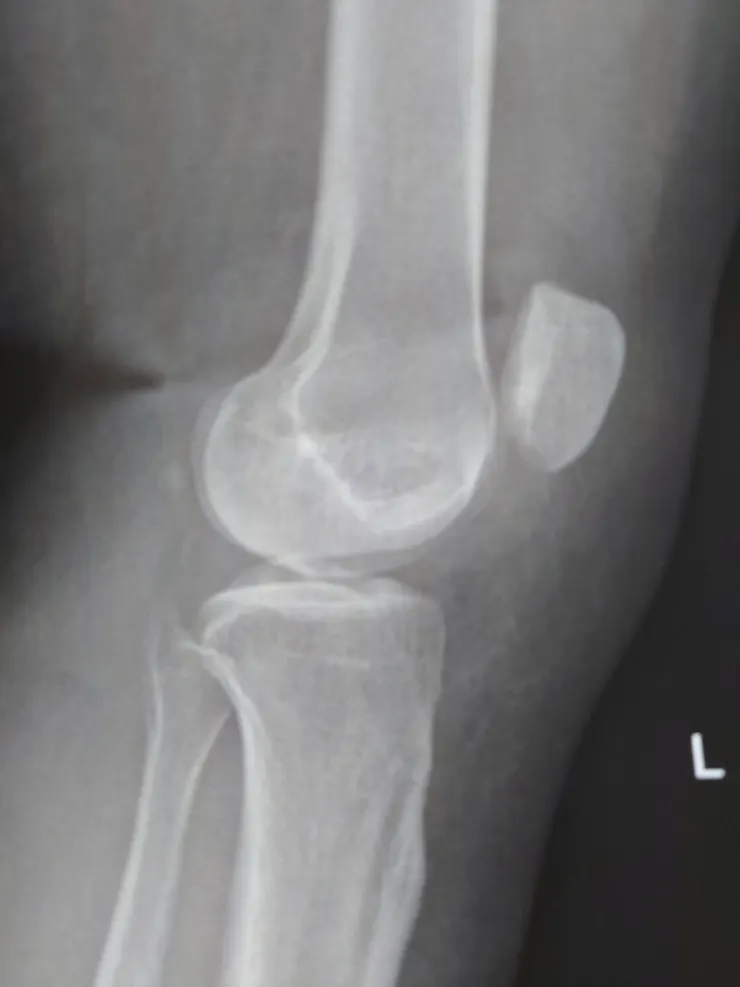

左側是我媽的膝蓋,右側是我的膝蓋

膝蓋位置過高

P1是受傷那天拍的照片,膝蓋明顯移位得很嚴重。P2和P3則記錄了逐漸消腫的情況。